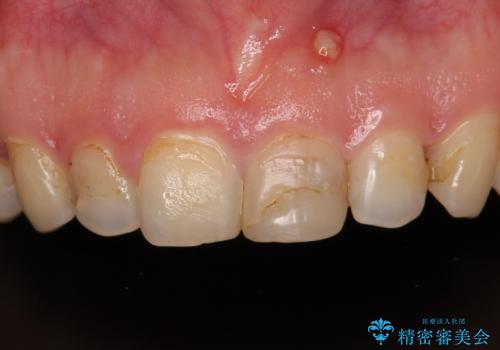

つぎはぎだらけの前歯をオールセラミッククラウンで自然な前歯に

- 前歯の色を気にして来院された患者様です。

むし歯で神経が取り除かれており、歯の変色と充填材の変色などにより、つぎはぎのような前歯となっていました。

膿の出口も認められたため、まずは根管治療を実施し、オールセラミッククラウンにて補綴治療を行うこととしました。